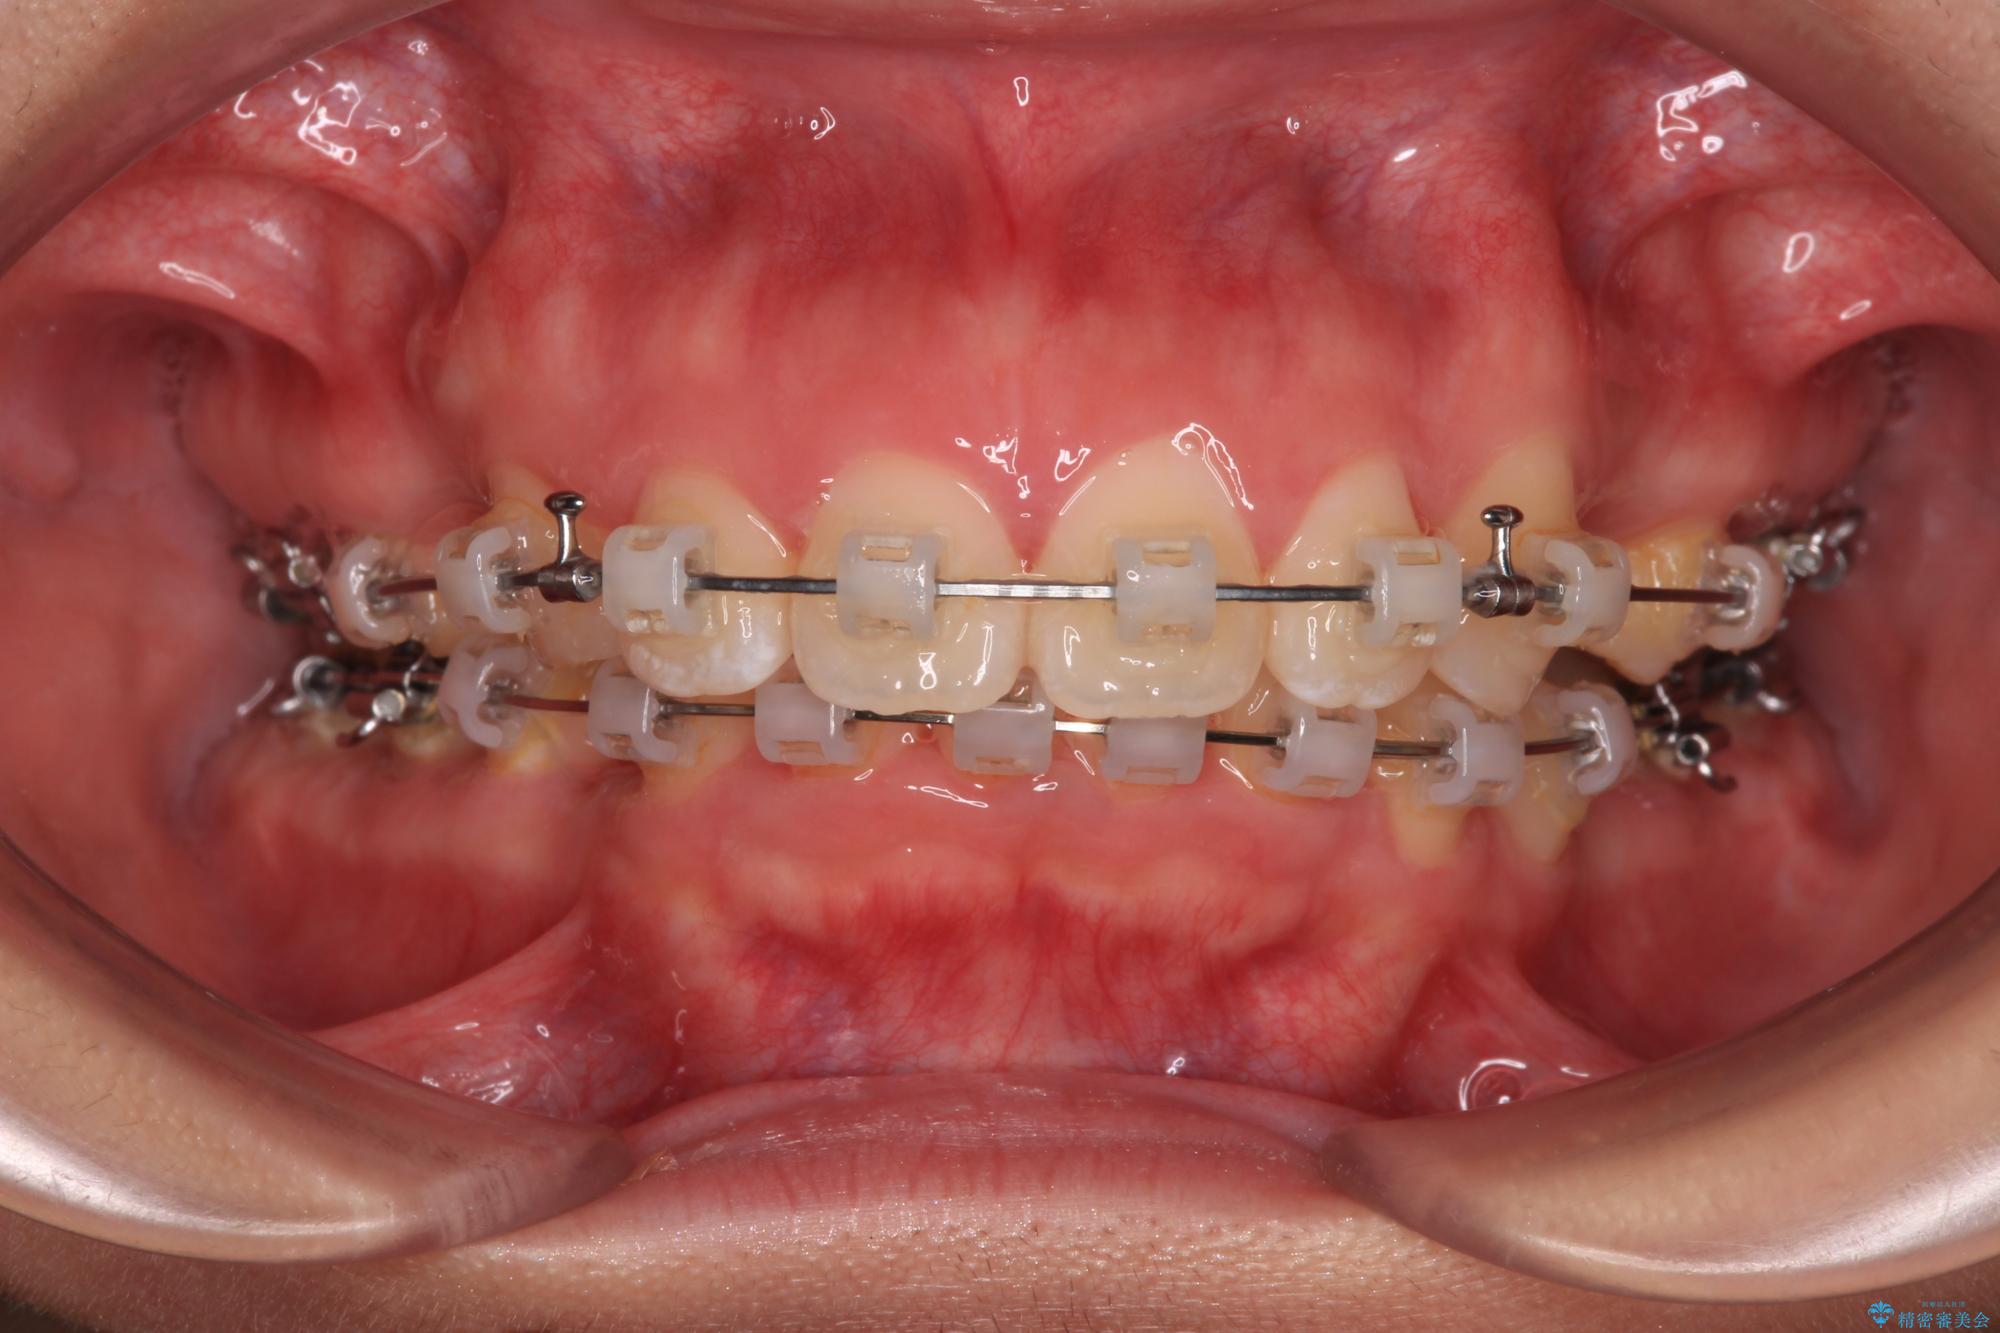

- 矯正装置

- クリアブラケット

- 上顎前歯が飛び出していて唇がうまく閉じられないとのことで来院された患者様です。

くちばしのように前歯が突出していたため、口元を積極的に引っ込めるために、上下左右の小臼歯4本を抜歯することとしました。

また、上顎歯列が下顎に対して前方位に位置していたため、補助装置を用いて上顎歯列を後方に移動させ、より積極的に口元を下げるようにしました。

上下正中位置を改善するため、左下はイレギュラーに第二小臼歯を抜歯しました。そのため治療期間の長期化が予想されましたが、2年半ほどで期待通りの歯列に仕上げることができました。